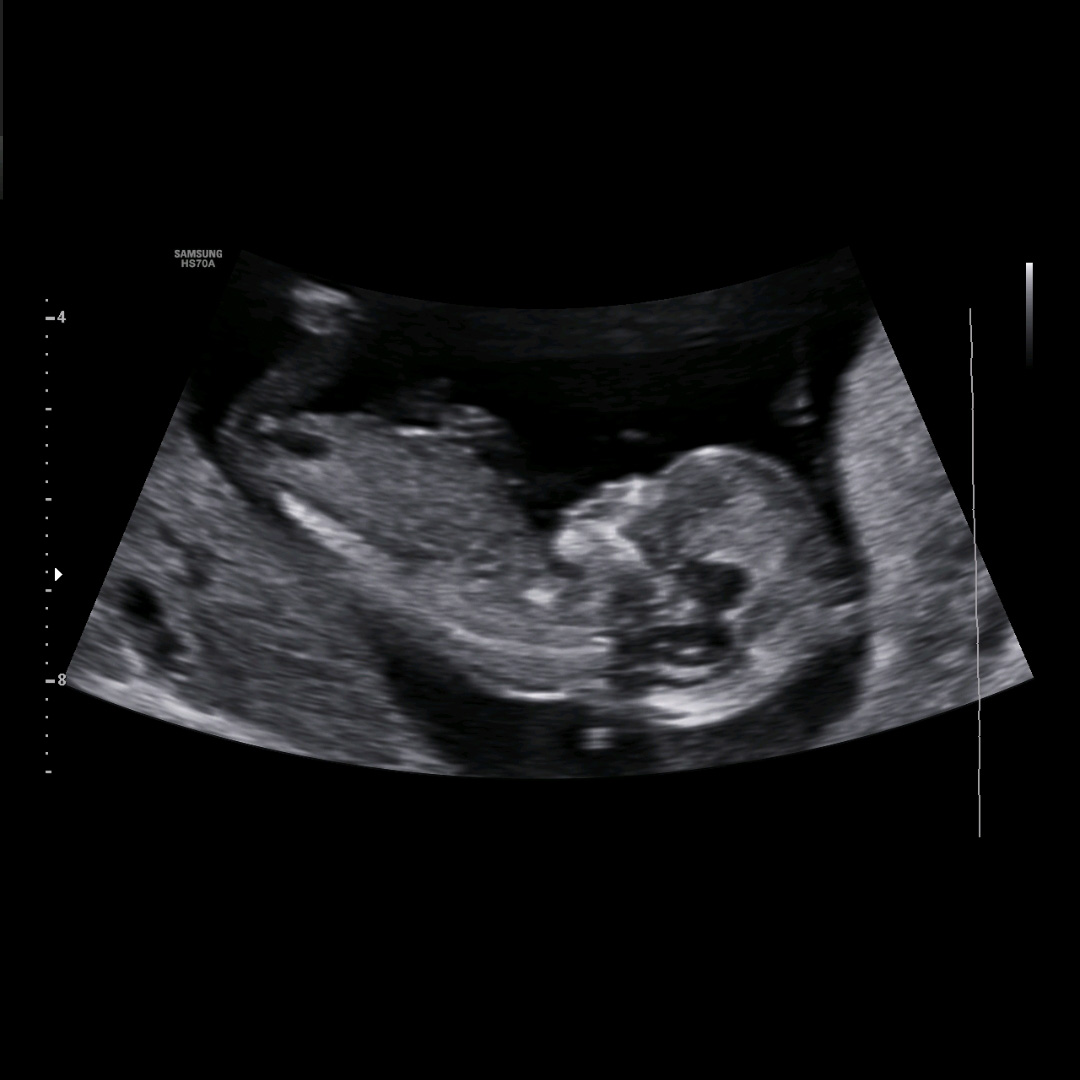

Echo's

Echo onderzoeken zijn onderdeel van de reguliere zwangerschapszorg. Ik ben geen echoscopist dus echo onderzoeken zullen plaatsvinden bij een echocentrum of andere (reguliere) verloskundige praktijk in de regio waar ik mee samen werk.

- “de termijnecho” tussen 10-12 weken om de uitgerekende datum vast te stellen

- “13 en/of 20 weken echo” als onderdeel van Prenatale screening

Andere echo’s worden vergoed op indicatie, bijvoorbeeld bij bloedverlies of twijfel over de groei bij deze of een eerdere zwangerschap:

- Rond 7-8 weken om te kijken of er een hartje klopt, het een kindje of meer kindjes zijn, de zwangerschap op de juiste plek zit en het de grootte heeft die je op basis van je laatste menstruatie zou verwachten.

- In het 3e trimester kijken we samen of er bij jou een reden is om met een of meerdere echo’s de groei en/of ligging van de baby te controleren. Bij iedere controle voel ik als verloskundige aan je buik en kijken we of echoscopisch onderzoek hierop kan aanvullen, bijvoorbeeld bij een op voorhand verhoogde kans of een signaal van afwijkende groei/vruchtwater/ligging/placentalocatie.